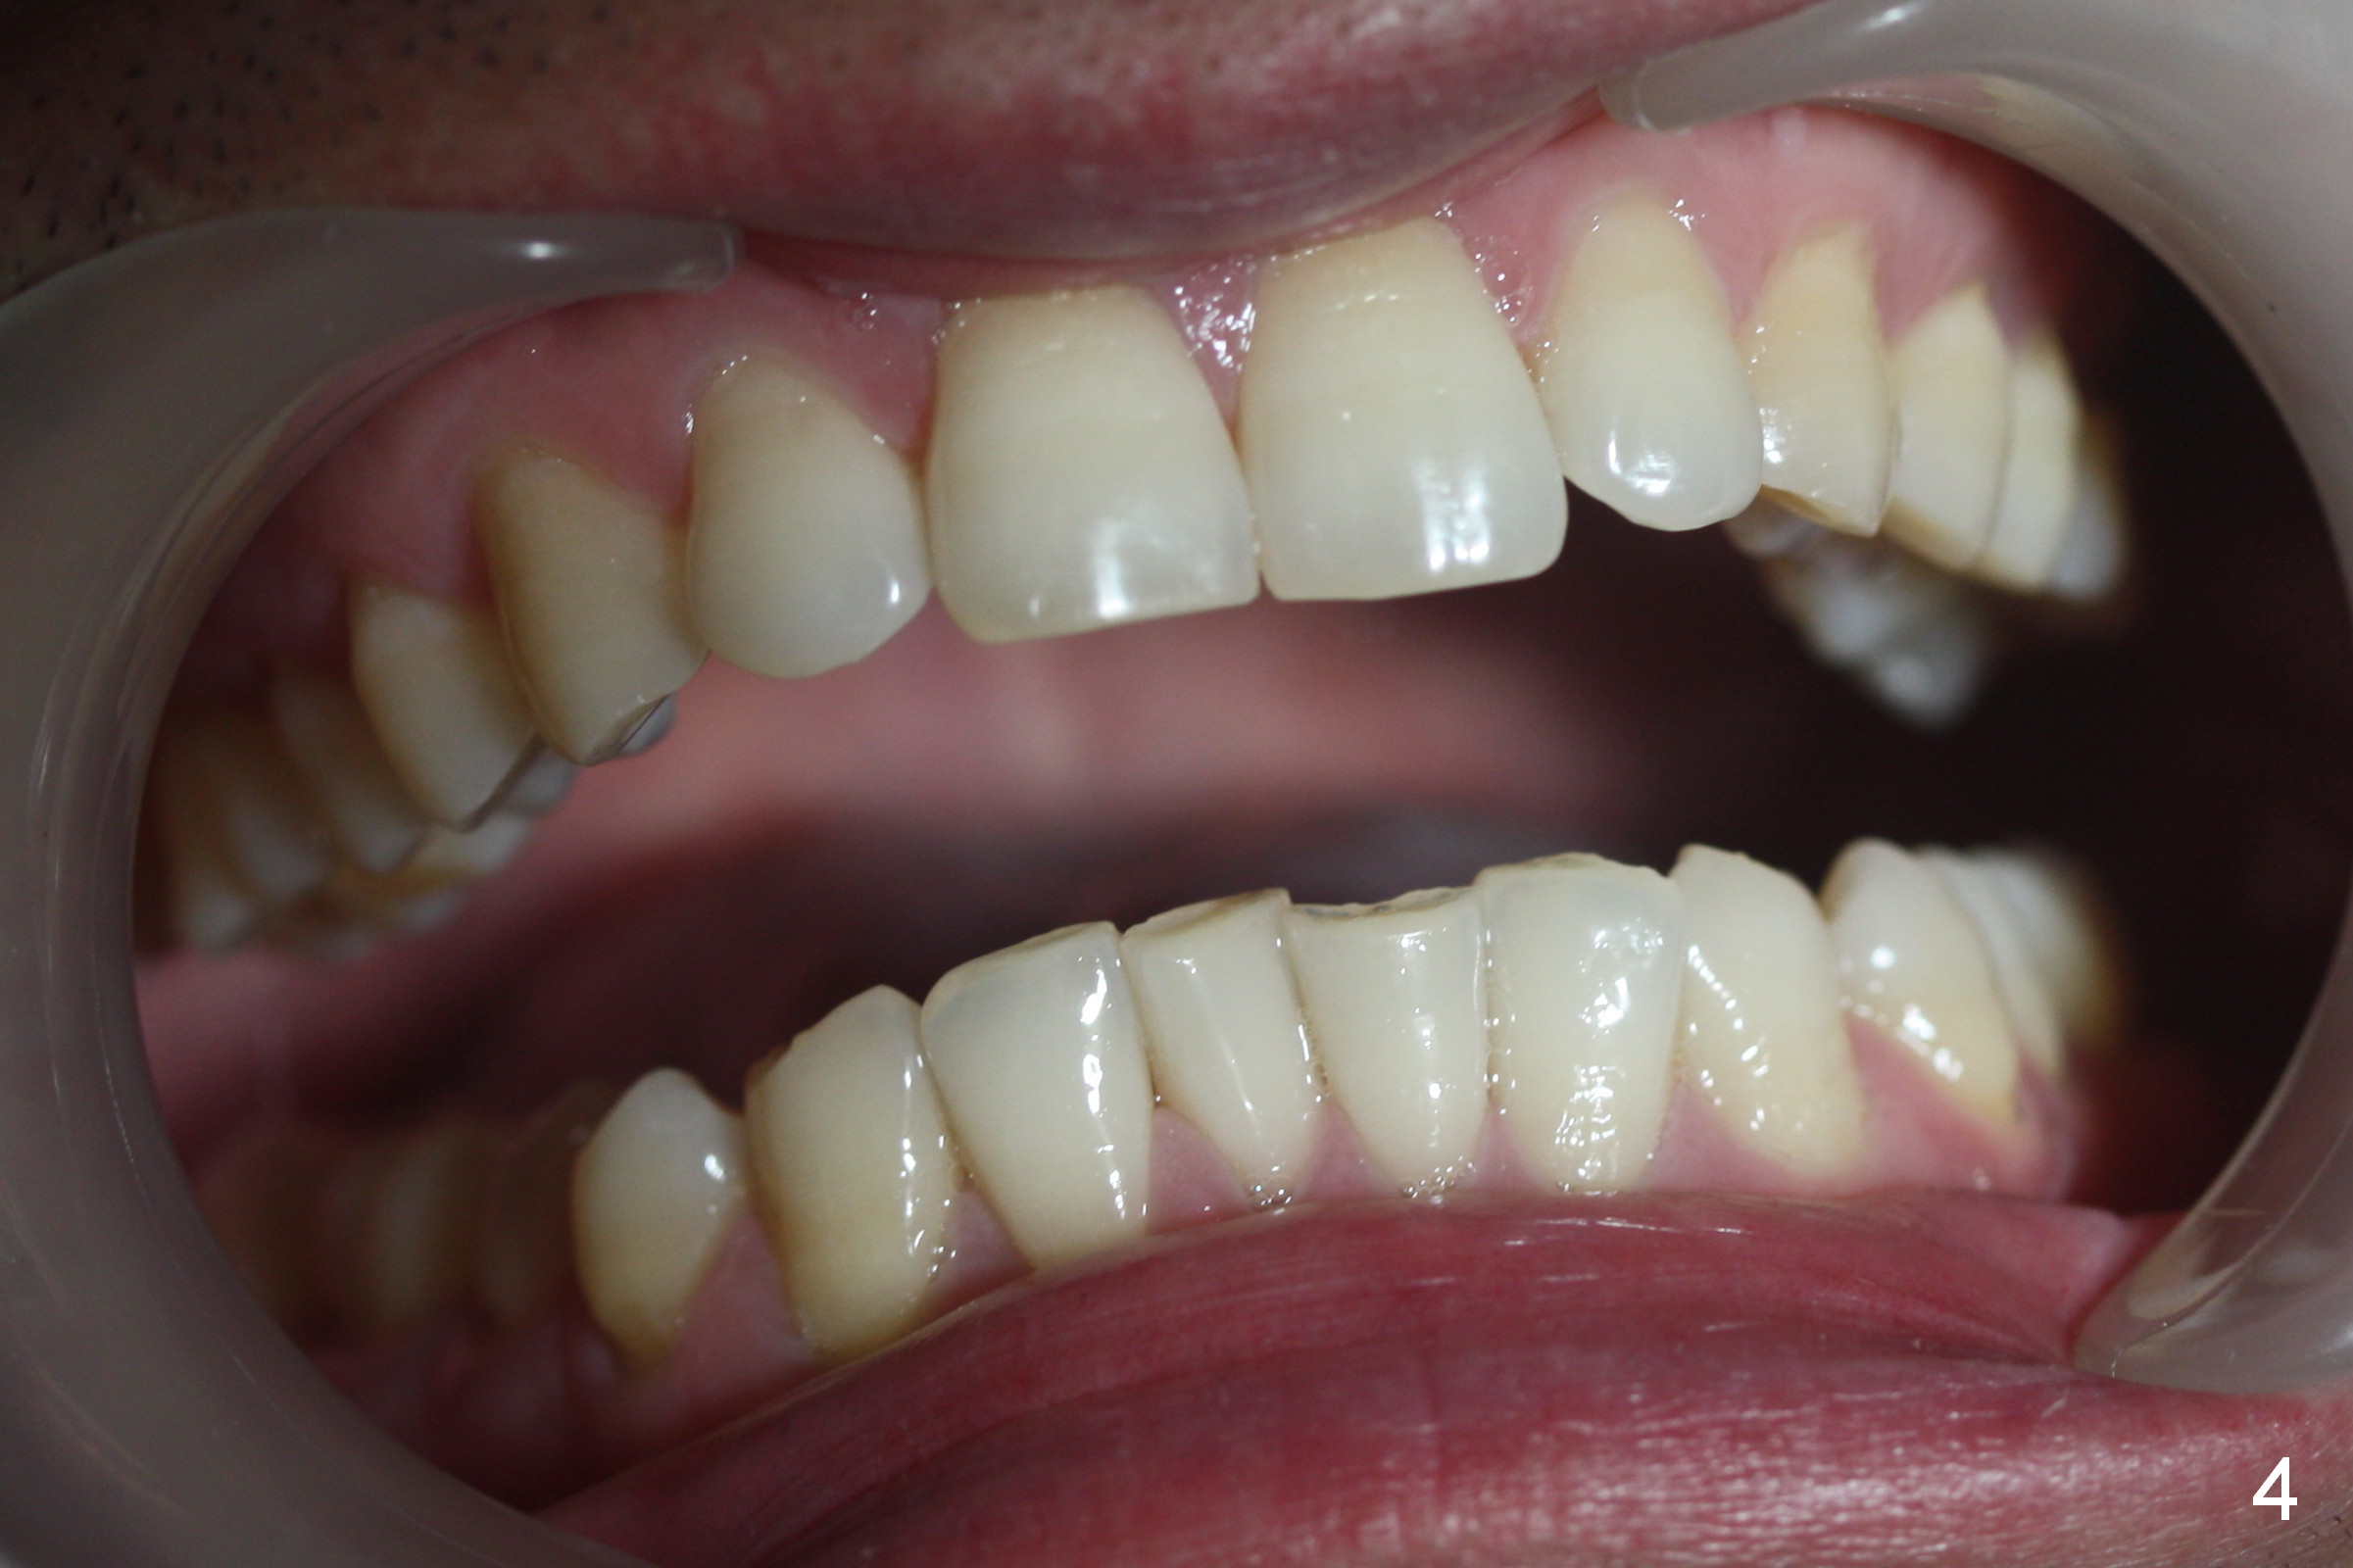

A 42-year-old man requests orthodontic treatment after extraction of the teeth #1, 16, 17, and 32, because it is easier for him to maintain oral hygiene post extraction. He thinks that orthodontic treatment will do the same. He appears to care about his dental alignment: not showing his teeth while smiling (Fig.2). The facial profile is within normal limit (Fig.3). His lower anterior teeth are moderately crowded (Fig.4) with anterior deep overbite and overjet (Fig.5,6). The deep overbite is more appreciated when the model is viewed posteriorly (Fig.7), approximately 90% of the upper incisors are covered by the lower anterior ones. More lingual surfaces are shown in another case before (Fig.8) and after (Fig.9) orthodontic treatment. With differential placement of brackets on the canines vs. incisors (Fig.6), the deep bite should be able to be corrected. Proximal reduction may be necessary.